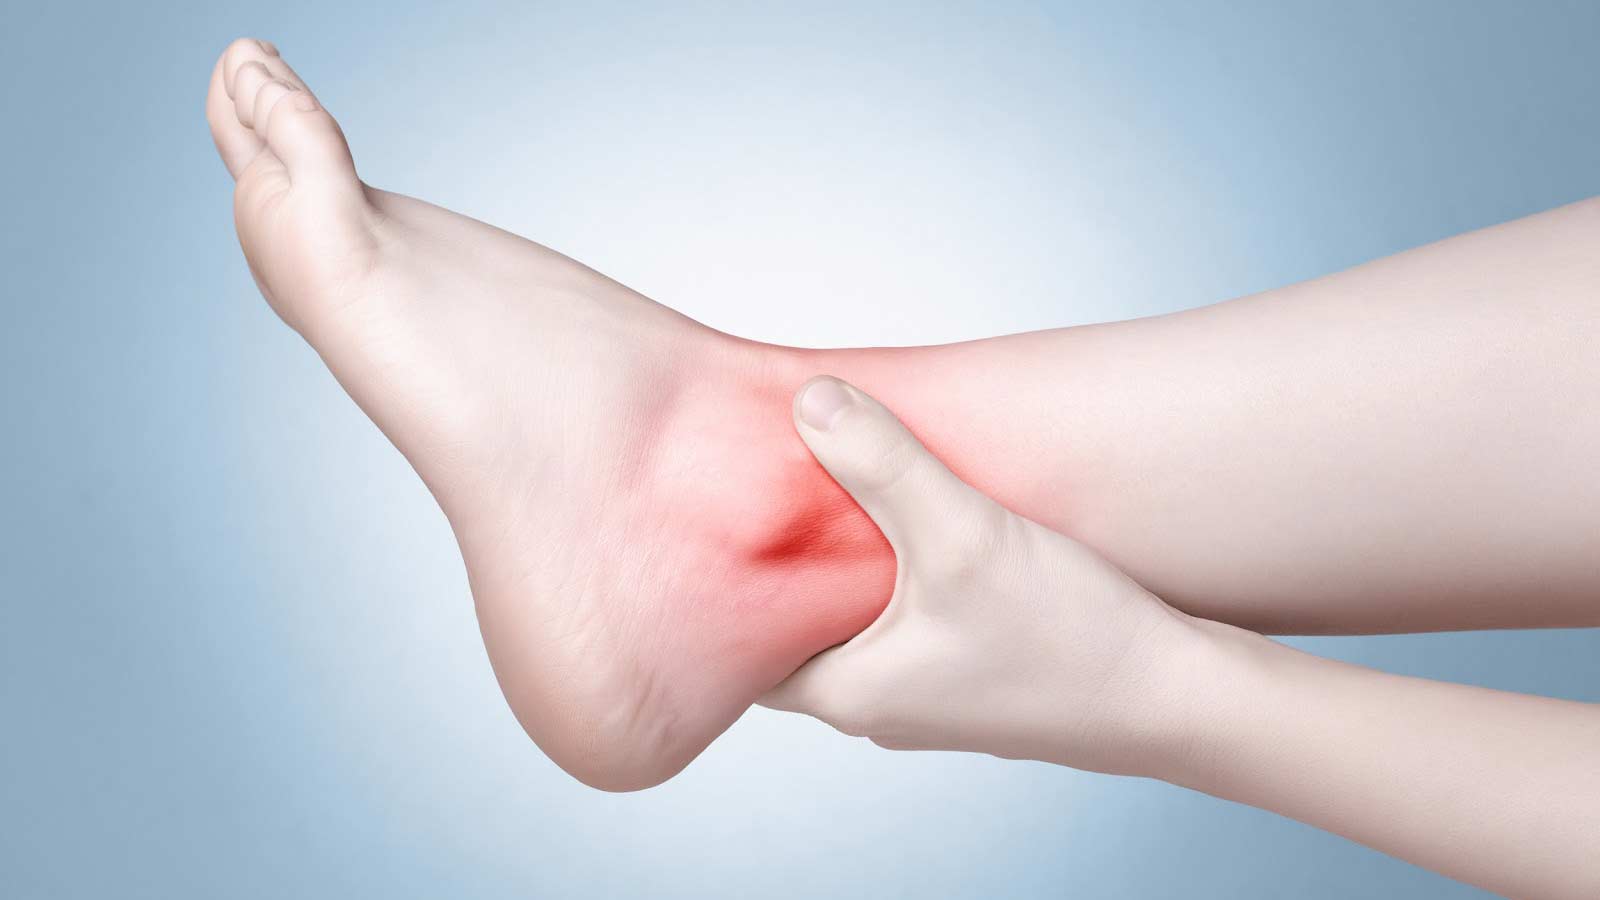

تورم در مچ پا اغلب به دلیل تجمع مایع در این نواحی به نام ادم ایجاد میشود.

تورم کف و قوزک پا در میان افراد سالمند و زنان باردار شایع است؛ اما در ورزشکاران و افرادی که بهواسطه شغلشان فعالیتهای بدنی زیادی دارند نیز دیده میشود. تورم پا تقریباً همیشه خفیف بوده و با چند راهکار ساده اما اصولی برطرف میشود.

درمان تورم پا و قوزک پا

اول باید مشخص کنید علائمتان چقدر شدت دارند. اگر تورمی که دارید شبیه تورمی است که بعد از مدت طولانی در یک وضعیت بدنی ثابت قرارگرفتن اتفاق میافتد پس با چند حرکت ساده میتوانید مشکل را رفع کنید.

اما اگر علائمتان ادامهدار شدند یا درد و کبودی دارید و یا راهرفتن برایتان سخت شده پس باید با پزشک مشورت کنید تا درمان مناسب را به شما توصیه کند. پزشک میتواند با معاینه فیزیکی و عکس با اشعه ایکس، نوع آسیب را مشخص کند.